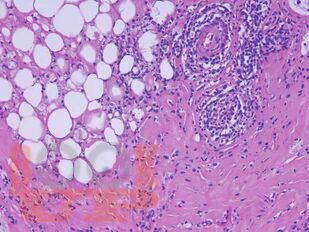

Атлас содержит авторские гистологические иллюстрации различных ревматических заболеваний, включая ревматоидный артрит, системную красную волчанку, системную склеродермию, а также редкие патологии: склеромикседему, IgG4‑ассоциированное заболевание, панникулиты, аутовоспалительный синдром, ассоциированный с адъювантами (ASIA‑синдром). Широко представлены системные васкулиты (болезнь Такаясу, гигантоклеточный артериит, узелковый полиартериит, гранулематоз с полиангиитом, эозинофильный гранулематоз с полиангиитом и др.). Гистологические препараты сопровождаются фотографиями пациентов.